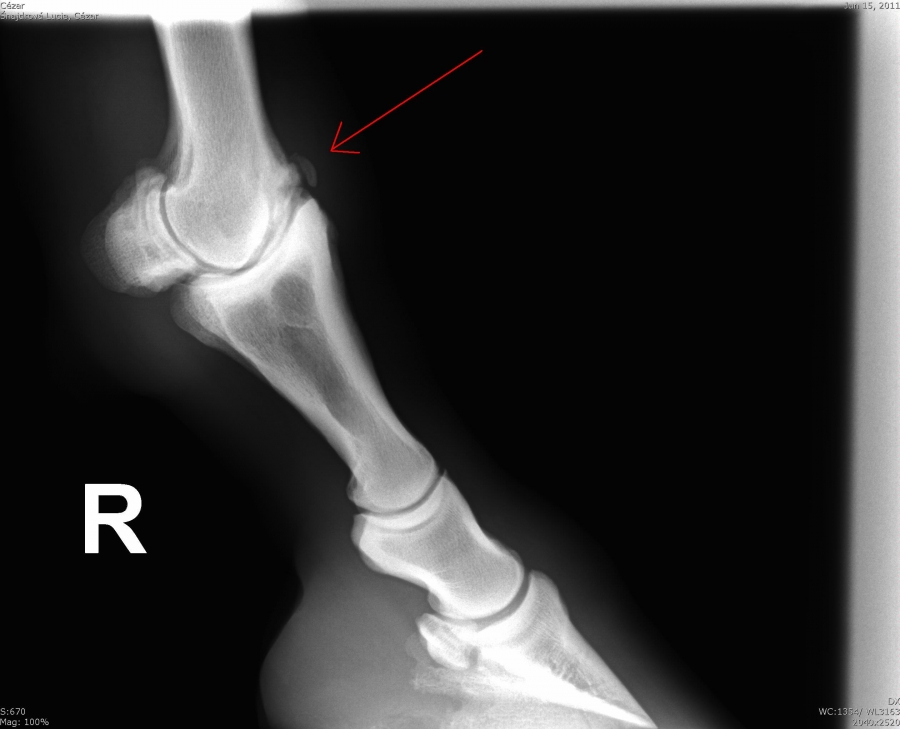

Čip ve spěnkovém kloubu na pánevní končetině

Ankylóza spěnkovýho kloubu